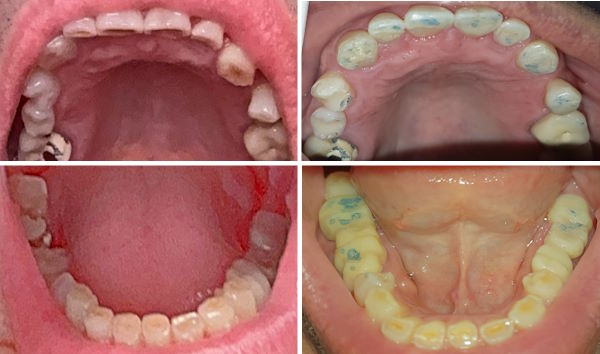

Bruxismus, Zigaretten und die schwierige Mundhygiene sind schuld an den Misserfolgen.

75-jährige Patientin (03.02.2026 / 1422)

Bei dieser Patientin hat der Bruxismus etwa 1 Zahn und 1 mm Zahnsubstanz pro 10 Jahre gekostet.

Die Füllungen und Wurzelbehandlungen haben etwa 10'000 CHF und

die Kronen, Brücken und das Implantat etwa 20'000 CHF gekostet.

Diese Schäden sind mehrheitlich nicht wegen Karies, sondern wegen dem Bruxismus entstanden.

Wurzelfraktur 4+ (2026) Brücke +345i (2017)

Zahnstatus (2026)